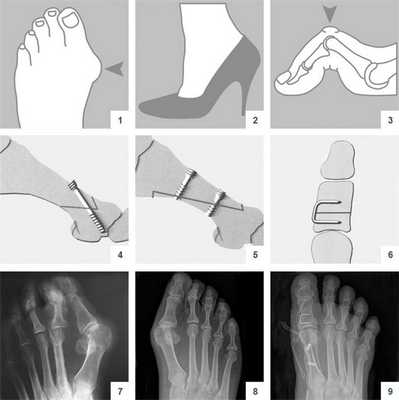

Реабилитация после операции халюс вальгус

Операция халюс вальгус — это удаление костного нароста на большом пальце стопы. Вальгусную деформацию провоцирует ношение остроносой обуви на каблуке. Также нарост может появиться по наследственным причинам. Из-за него нарушается биомеханика сустава, ходить становится больно, и сустав быстро изнашивается. Халюс вальгус лечат консервативным и хирургическим путем. Во время операции по реконструкции — остеотомии — корректируют ось кости и форму мягких тканей так, чтобы большой палец сохранял прямое положение. Реабилитация после операции халюс вальгус напрямую влияет на длительность сохранения результата. Если пациент следует рекомендациям реабилитолога и избегает ношения остроносой обуви, эффект сохраняется на всю жизнь.

Консервативные методы эффективны на самой ранней стадии вальгусной деформации стопы. Если момент упущен, и наступать на большой палец становится все больнее, назначают хирургическую коррекцию и приступают к реабилитации после операции халюс вальгус с винтами.

Хирургическое лечение вальгусной деформации стопы: операция по удалению шишки

В литературе можно найти описание более чем 400 методик оперативного лечения халлюс-вальгуса. В прошлом ортопеды боролись с вальгусной деформацией путем хирургического удаления суставных головок, что приводило к серьезному нарушению функций стопы. Поэтому сегодня врачи предпочитают делать менее травматичные операции.

Что такое вальгусная деформация? Вначале Hallux Valgus вызывает искривление только большого пальца стопы. В результате у человека увеличивается нагрузка на головки 2-4 плюсневых костей, что ведет к молоткообразной деформации II-V пальцев. Своевременное хирургическое лечение помогает избежать этого неприятного явления.

Виды операций на стопе

Операции, которые делают при вальгусной деформации, можно условно разделить на малоинвазивные и реконструктивные. Первые менее травматичны, однако эффективны только при экзостозах и начальной деформации. Малоинвазивные хирургические вмешательства выполняют через два-три прокола размером 3-4 мм.

Таблица 1. Виды операций.

| Особенности проведения | Показания | |

| На мягких тканях | Во время операции врач работает только с мышцами, сухожилиями и суставной сумкой. | Hallux Valgus I степени без деформации головки плюсневой кости. |

| На костях | Суть таких хирургических вмешательств заключается в подпиливании костей и/или выполнении остеотомии. | Вальгусная деформация II-III степени. |

| Комбинированные | Подразумевают одновременное удаление костных наростов и пластику связок. | Выраженный Hallux Valgus с нарушением функций стопы. |

Во время малоинвазивных операций хирург использует микроинструменты, позволяющие выполнять сложные манипуляции со связками и суставной капсулой. При необходимости он подпиливает кости с помощью микрофрез, которые отдаленно напоминают стоматологический инструментарий.

Название хирургических техник

На начальных стадиях болезни врачи стараются делать малоинвазивные операции. После них пациент быстро восстанавливается и уже через 3-4 недели возвращается к привычному образу жизни. При запущенной вальгусной деформации возникает необходимость в более сложных хирургических вмешательствах.

Давайте посмотрим, какие из них чаще всего используют в современной ортопедии.

Операция McBride

Наиболее популярна среди всех хирургических вмешательств на мягких тканях стопы. Ее суть заключается в перемещении сухожилия m. adductor halluces на головку I плюсневой кости. Это позволяет сблизить между собой кости плюсны и восстановить нормальный мышечно-сухожильный баланс стопы.

К сожалению, отводящая мышца первого пальца неспособна противодействовать постоянной нагрузке. Именно поэтому частота рецидивов после операции McBride довольно высока. Если человек не устраняет действие провоцирующих факторов - у него вскоре снова развивается Hallux Valgus. Избежать этого помогает ношение ортопедической обуви, отказ от каблуков и тяжелой физической работы.

При ярко выраженных деформациях операцию McBride дополняют остеотомией I плюсневой кости SCARF.

Относится к миниинвазивным операциям. Во время хирургического вмешательства больным выполняют поперечную остеотомию через кожный разрез длиной 1 см. После этого дистальный костный фрагмент смещают в латеральном направлении и фиксируют с помощью специальной спицы.

CHEVRON

В ходе операции хирург выполняет V-образую остеотомию. Он перепиливает первую плюсневую кость в области головки, а костные фрагменты соединяет с помощью специальных титановых винтов. Поскольку фиксация очень прочная, в послеоперационном периоде пациент не нуждается в гипсовой иммобилизации.

Отметим, что Chevron-остеотомия эффективна только при незначительной деформации первого пальца стопы. В наше время в ортопедии ее используют все реже. Вместо нее большинство врачей делает Scarf-остеотомию.

SCARF

Z-образная остеотомия Scarf - это золотой стандарт лечения вальгусной деформации. Она позволяет установить головку плюсневой кости под нужным углом. В ходе хирургического вмешательства врачи также убирают деформацию суставной капсулы и меняют направление некоторых сухожилий.

Когда операции Scarf недостаточно - хирурги делают проксимальную клиновидную остеотомию или артродез.

Важно! У большинства пациентов с вальгусной деформацией врачи выявляют костную мозоль (экзостоз). Нарост локализуется на медиальной поверхности головки I плюсневой кости. Как правило, его удаляют во время всех операций, в том числе и малоинвазивных.

Не путайте спиливание костного нароста с остеотомией. Это две совершенно разные манипуляции. Цель первой - убрать косметический дефект, второй - восстановить нормальное функциональное состояние стопы. Помните, что удаление костной мозоли (операция Шеде) не в состоянии излечить вас от Hallux Valgus.

Артродез при вальгусной деформации

Артродезирование - это полное обездвиживание плюсне-клиновидного сустава путем соединения формирующих его костей. Операцию делают лицам с поперечно-распластанной деформацией и Hallux Valgus с гипермобильностью I плюсне-клиновидного сустава.

Артродез - это наиболее травматичная операция, подразумевающая полное удаление плюсне-клиновидного сустава. Ее делают только в крайнем случае, когда другие методы оказываются неэффективными.

Операция молоткообразной деформация пальцев ног

Как известно, на поздних стадиях Hallux Valgus сочетается с молоткообразной деформацией II-V пальцев. Она выглядит непривлекательно и негативно сказывается на функциях стопы. Для ее исправления используют целый ряд хирургических вмешательств.

В лечении молоткообразной деформации наиболее эффективна остеотомия. Именно ее выполняют в самых тяжелых и запущенных случаях.

Восстановительный период

Вставать с постели пациентам разрешают уже на следующий день после операции. Первое время ходить им разрешают только в туфлях Барука.

В первые дни после хирургического вмешательства больные находятся под наблюдением лечащего врача. Из стационара их выписывают на 2-3 сутки. Если во время операции человеку накладывали нерассасывающиеся швы - их снимают на 10-14 день.

Что касается обуви, пациентам требуется как минимум 3 месяца носить ортопедические стельки. Надевать каблуки можно лишь спустя полгода после хирургического вмешательства. При этом их высота не должна превышать 6 см.